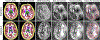

Despite advances in data augmentation and transfer learning, convolutional neural networks (CNNs) difficultly generalise to unseen domains. When segmenting brain scans, CNNs are highly sensitive to changes in resolution and contrast: even within the same MRI modality, performance can decrease across datasets. Here we introduce SynthSeg, the first segmentation CNN robust against changes in contrast and resolution. SynthSeg is trained with synthetic data sampled from a generative model conditioned on segmentations. Crucially, we adopt a domain randomisation strategy where we fully randomise the contrast and resolution of the synthetic training data. Consequently, SynthSeg can segment real scans from a wide range of target domains without retraining or fine-tuning, which enables straightforward analysis of huge amounts of heterogeneous clinical data. Because SynthSeg only requires segmentations to be trained (no images), it can learn from labels obtained by automated methods on diverse populations (e.g., ageing and diseased), thus achieving robustness to a wide range of morphological variability. We demonstrate SynthSeg on 5,000 scans of six modalities (including CT) and ten resolutions, where it exhibits unparallelled generalisation compared with supervised CNNs, state-of-the-art domain adaptation, and Bayesian segmentation. Finally, we demonstrate the generalisability of SynthSeg by applying it to cardiac MRI and CT scans.